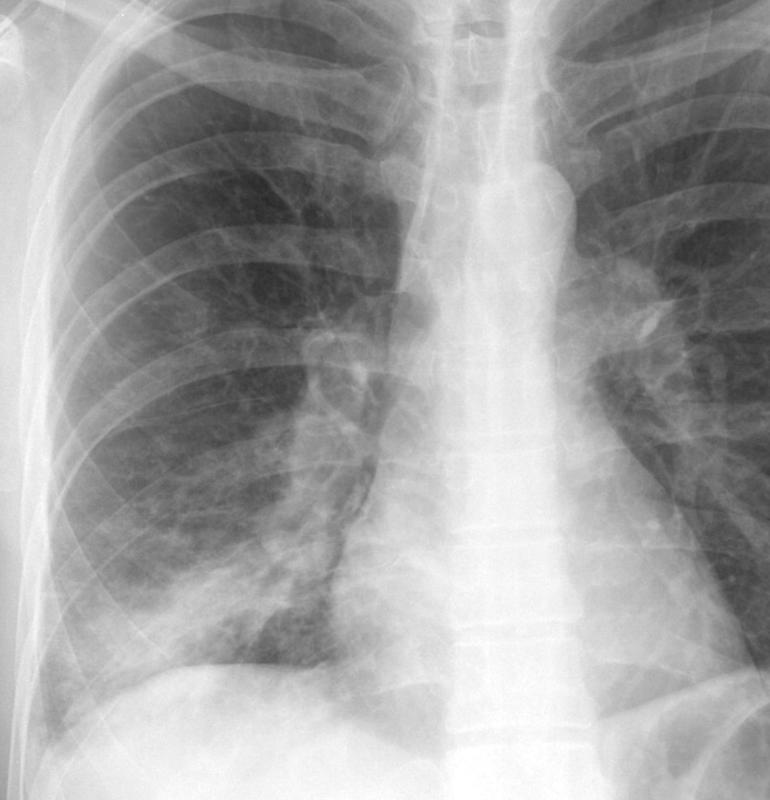

Gallery Pneumonia Case 9 RLL brpneum PA

Case 9 RLL brpneum PA